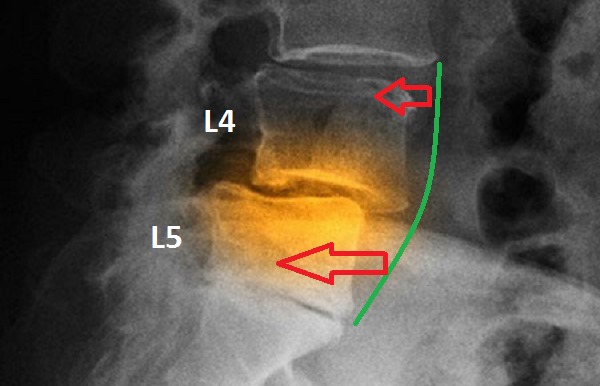

Диагноз ретролистез устанавливается, когда позвонки смещаются относительно самой структуры позвоночника. Наиболее уязвимым в этом плане является пятый поясничный позвонок, так как в его области наблюдается определённый изгиб.

На самом деле, любой из позвонков может сместиться, однако чаще всего поражается именно поясничный отдел, а именно L4 и L5, а также шейный отдел. Поэтому позвонок L5 при ретролистезе представляет собой ключевую область для изучения данной болезни.

Первая степень ретролистеза определяется смещением позвонка относительно нижележащего на четверть, что составляет 25%. Вторая степень характеризуется смещением половины позвонка. На третьей степени происходит смещение на 75%. Наконец, на четвёртой степени позвонок полностью выпадает.

Для диагностики смещения позвоночника обязательно проводится рентгенологическое исследование.